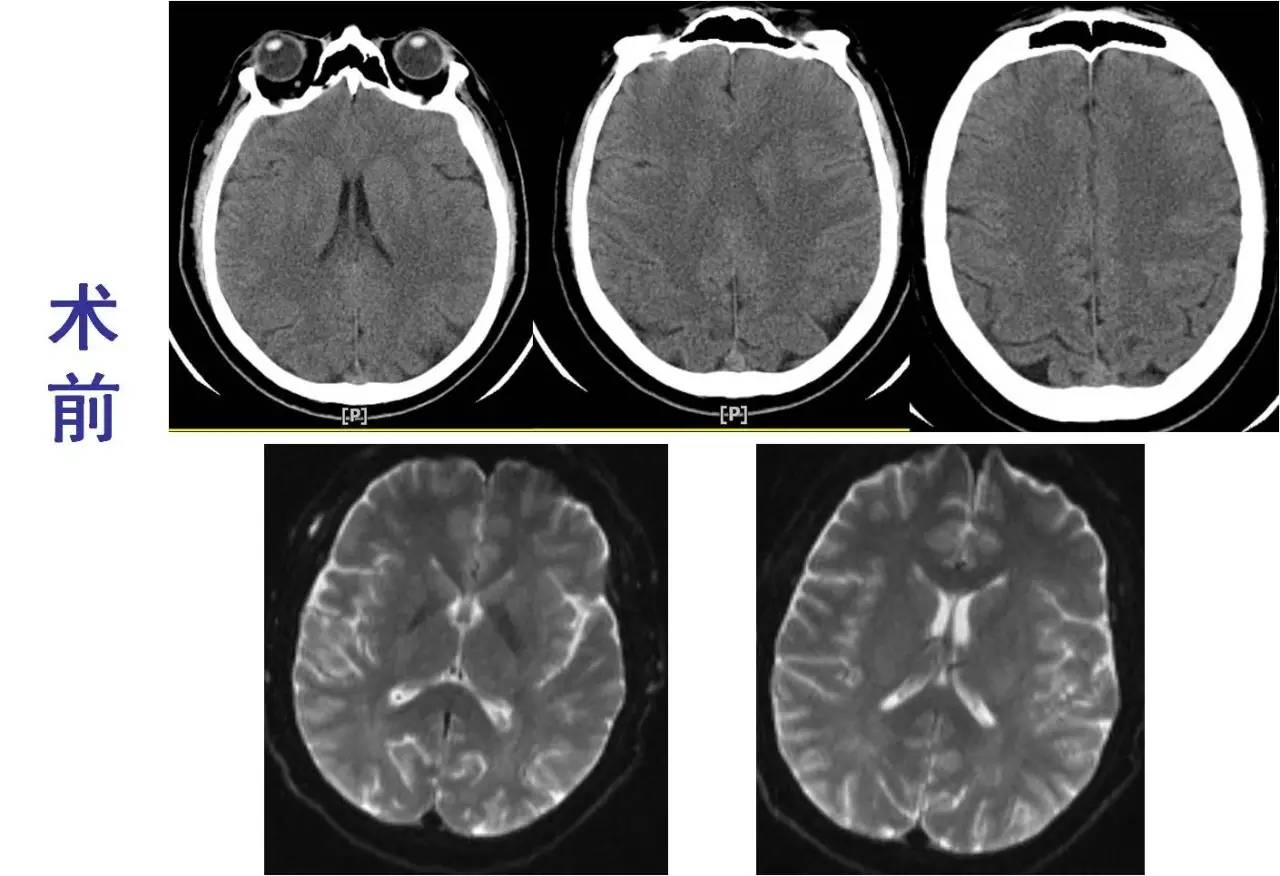

》男性,47岁,SIE;

》UCG:主动脉瓣关闭不全,赘生物;

》突发言语不能、右侧肢体活动不能;

》查体:运动性失语,右侧肌张力低,右侧肌力0级,右侧巴氏征阳性 。NIHSS评分18分;

》CT:颅内未见出血;

》DSA:左侧大脑中动脉闭塞。

术前

术后

》意识清楚,言语流利,四肢活动自如;

》四肢肌力Ⅴ级;

》术后24小时NIHSS评分:0分;

》5天后主动脉换瓣术;

》90天mRS评分0分。